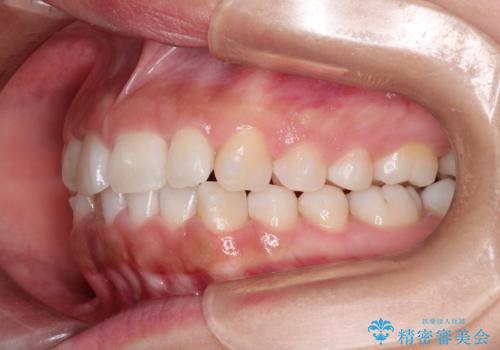

- 初診時には前歯部に捻転や叢生、臼歯部にも一部叢生が見られる状態でした。

インビザラインでの治療を計画し、行っていきました。

インビザライン治療により、捻転を含む歯列もしっかりと改善しています。

基本的な不正咬合部分は初回の30枚のマウスピースでほぼ改善しており、リファインメントでは前歯部の細かな調整など、患者様の要望を取り入れる形でシミュレーションをセットアップし、満足の行く結果に仕上がりました。